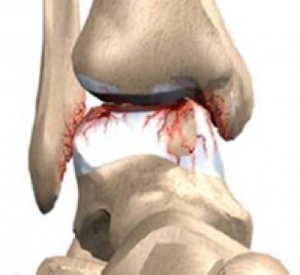

b) L’impingement antero-laterale si osserva a livello di un recesso sinoviale localizzato tra tre strutture ossee: tibia, fibula e astragalo; tale area anatomica è delimitata anteriormente dal legamento tibio-peroneale antero-inferiore e dal legamento peroneo-astragalico anteriore, ed inferiormente dal legamento peroneo-calcaneale. La sindrome è caratterizzata da dolore cronico in sede laterale esacerbato durante l’eversione o la dorsiflessione del piede, e dal salto su un piede. L’esame clinico documenta dolore nella regione antero-laterale del piede e tumefazione nelle fasi più avanzate. L’impingement può essere causato da un solo trauma o da microtraumi ripetuti. La distorsione di caviglia è universalmente considerata uno dei più comuni traumi osservati; si ha soprattutto durante l’attività sportiva ed è più frequente soprattutto nei giocatori di basket e nei calciatori, e nella maggior parte dei casi si tratta di pazienti che hanno meno di 35 anni. Nell’85% dei casi, l’evento traumatico si ha in inversione e coinvolge il complesso legamentoso laterale, nel quale il legamento più facilmente colpito è il legamento peroneo-astragalico anteriore.

Il trattamento conservativo porta alla guarigione senza complicanze nella maggior parte dei casi; tuttavia si è stimato che circa il 3% delle distorsioni di caviglia può portare ad una sindrome da impingement antero-laterale. Un trauma in inversione con almeno una lesione parziale del legamento talo-fibulare anteriore può determinare un danno con conseguente reazione infiammatoria della sinovia a livello dell’interlinea articolare antero-laterale. In assenza di un adeguato trattamento di immobilizzazione o di riabilitazione, può aversi ipertrofia e fibrosi cicatriziale a livello della sinovia. La cronicizzazione di questi fenomeni può portare allo sviluppo di una proliferazione che si estende nel recesso antero-laterale e che causa impingement meccanico e dolore. Più raramente questa massa può determinare l’erosione della porzione antero-laterale del domo astragalico, con conseguente sviluppo di foci di condromalacia. Oltre all’ispessimento ed alla deformità cicatriziale del legamento tibio-fibulare anteriore, la RM eseguita su piani di scansione assiali e sagittali, mostra, soprattutto in presenza di versamento intra-articolare, un’intensità di segnale intermedia del tessuto sinoviale sia nelle sequenze T1 che T2 pesate . RM ed artro-RM, soprattutto in presenza di versamento intra-articolare, sono in grado di documentare sia l’ipertrofia sinoviale, causa di impingement antero-laterale, che eventuali lesioni cartilaginee, ossee e legamentose associate.